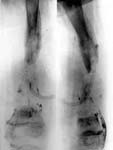

4.Больная в аппарате Илизарова.

5.Результат лечения.